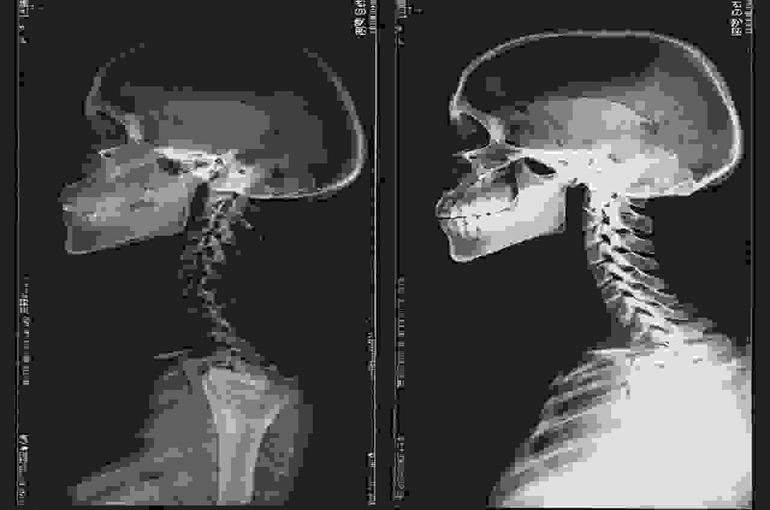

ストレートネックとは、本来緩やかなS字カーブを描いているはずの首の骨、すなわち頸椎が、何らかの原因によってその自然な湾曲を失い、まっすぐになってしまっている状態を指します。

レントゲン検査などで頸椎の角度を測定することで、ストレートネックの状態が確認されることがあります。